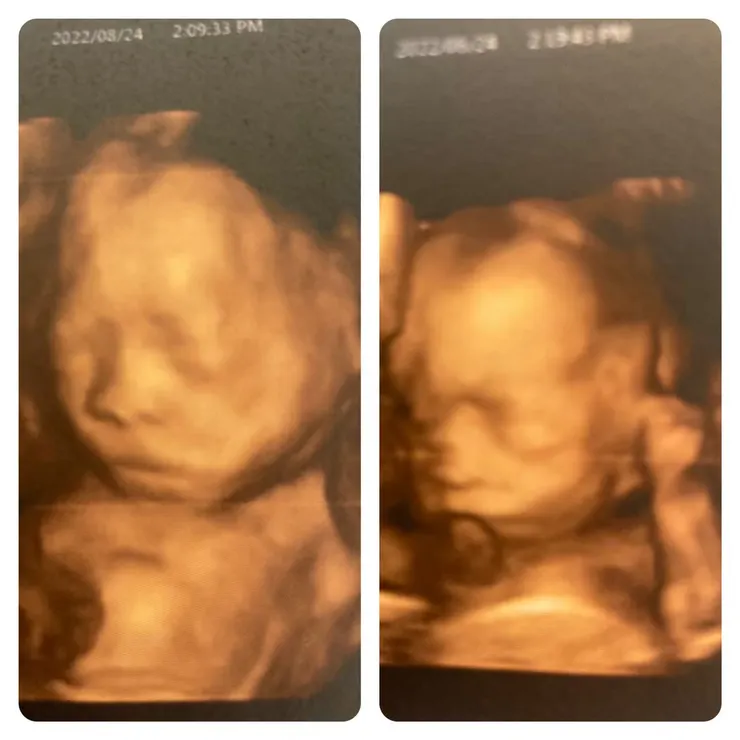

在媺嫚媽媽感受到🦶🦶的力道都不大,肚皮的起伏很小,每次的胎動都讓我感動與興奮,是妳們在告訴媽媽,我們在這唷!我們很健康,媽媽不要擔心,胎動是讓媺嫚媽媽放心的證明。

嫚嫚在子宮裡是活潑的孩子,每天都能感受到她小小的翻動,肚皮晃動的部分固定是左邊👈,媺媺在子宮裡是安靜的小孩,很少動常常讓我感受不到她的存在,媺嫚媽媽會很不放心,常常用手很大力的拍打肚子,過1.2分鐘才能得到媺媺的回應,意思意思動1.2下,回應媽媽。